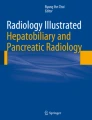

Hepatic and splenic iron overload. Dual gradient-echo images of iron deposition in a patient who has received multiple blood transfusions. (a) Out-of-phase, (b) in-phase images. Due to dephasing of protons as a result of magnetic field inhomogeneity in the presence of iron, signal drop occurs within the liver parenchyma between the first (out-of-phase) and second (in-phase) echoes. Similar change is seen within the spleen as a result of iron deposition within the reticuloendothelial system following chronic transfusions. (c) Formal measurement of liver iron concentration. ROI placement on the R2* map derived using the multi-echo IDEAL IQ (GE) technique allows for liver iron concentration measurement, following conversion using a calibration formula. In this case, the R2* value = 341 s−1 (Normal <67 s−1 at 1.5 T), equivalent to 8.9 mg Fe/g dry liver (normal <1.8 mg Fe/g)—equivalent to severe overload